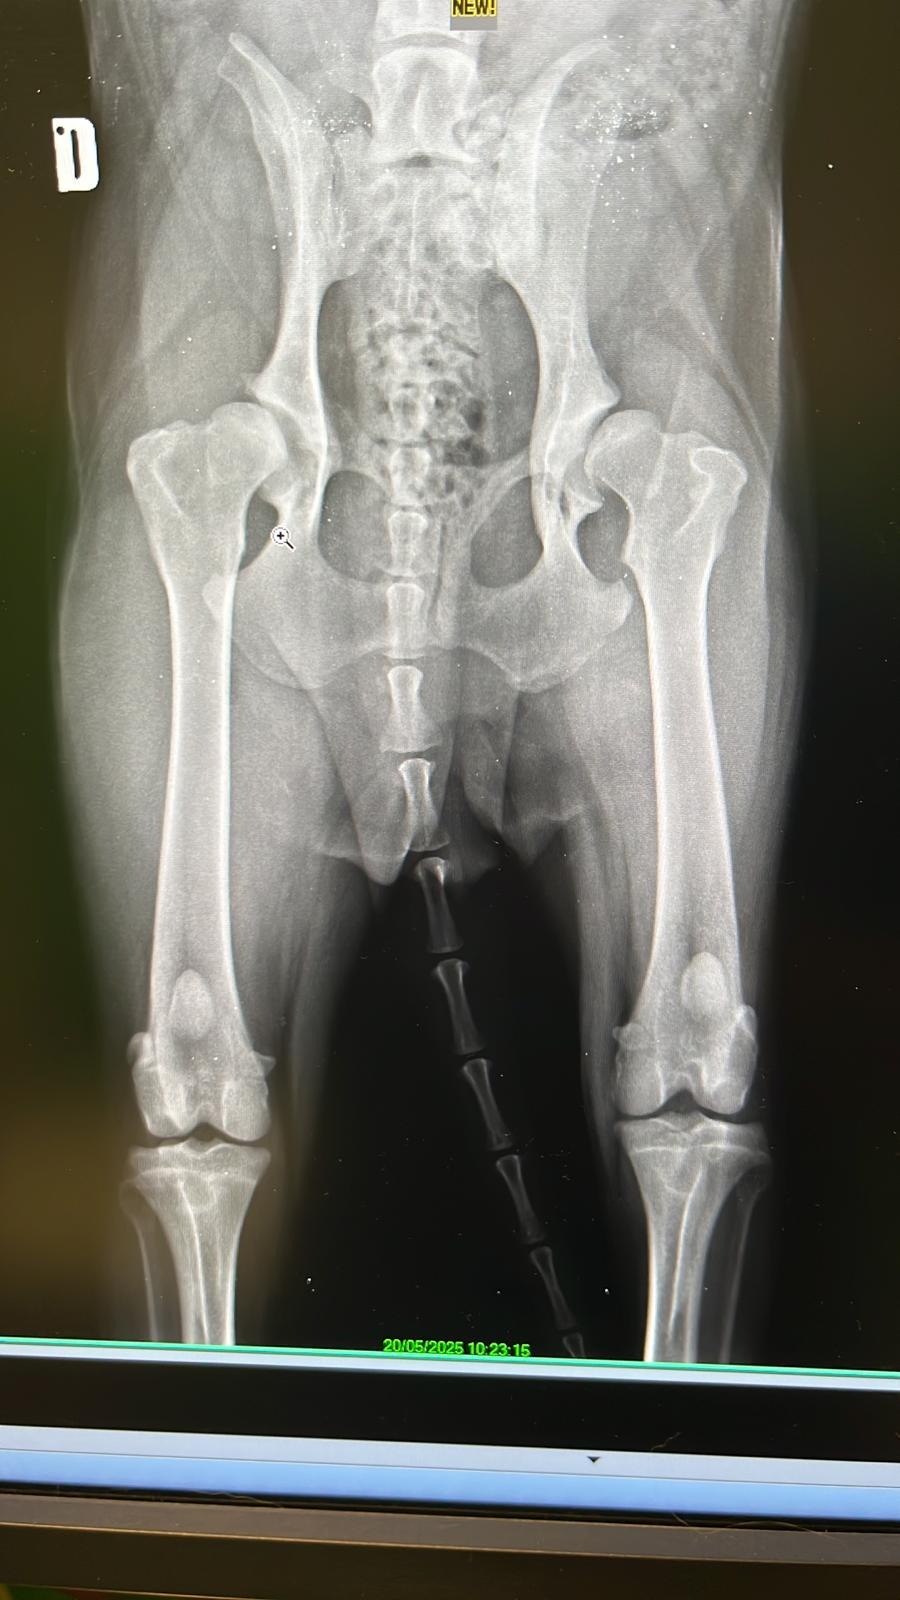

Purtroppo la mia situazione è un disastro: ho un brutto problema all'anca sinistra e alla regione sacroiliaca, non appoggio la zampa e non ho muscolo, la diastasi sacroiliaca non si sa se sia conseguente ad un investimento o a delle botte, ma sicuramente ha origine traumatica, sarà necessario effettuare una risonanza magnetica e una visita neurologica per capire se e come procedere per inserire una protesi nella mia anca che mi permetta di camminare e mi possa dare una vita "normale".